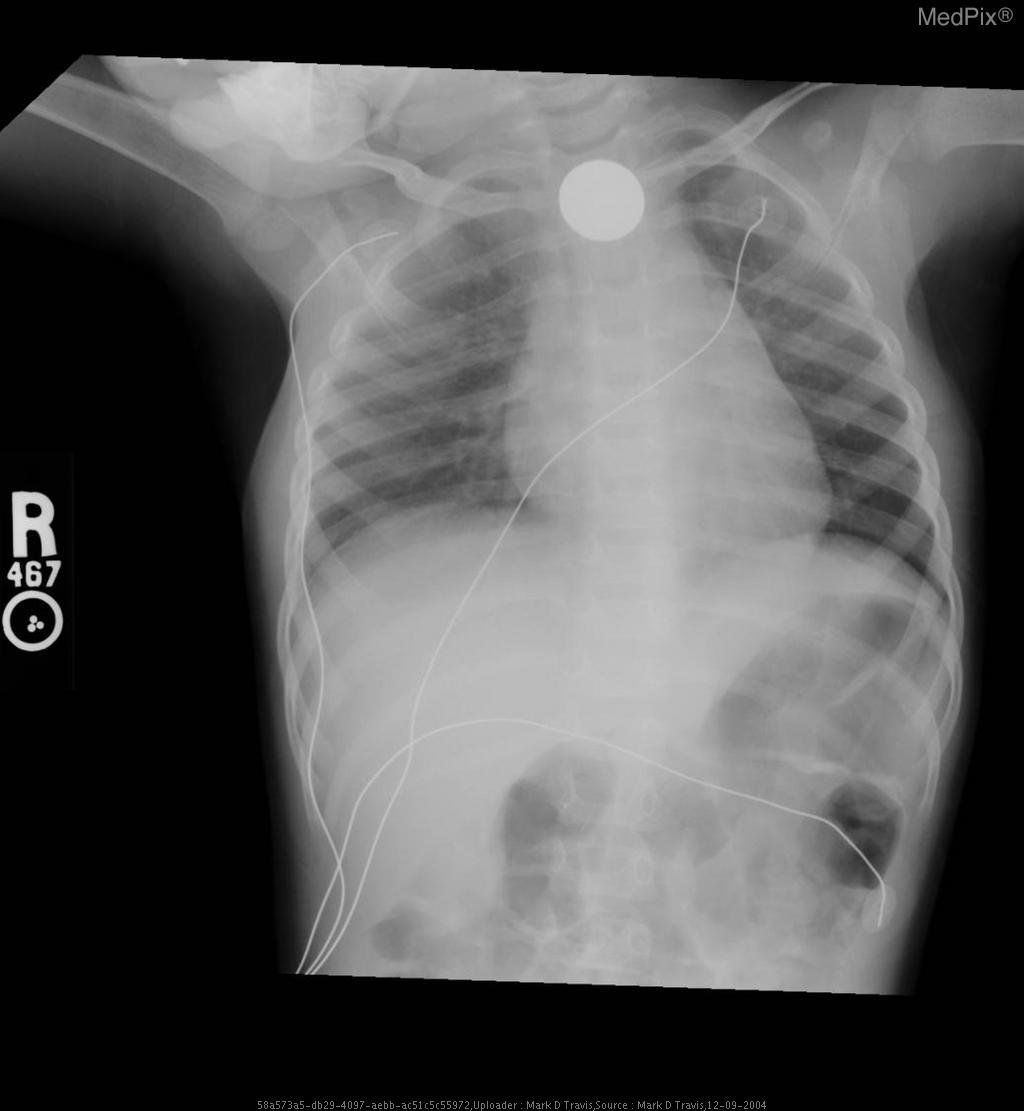

Esophageal foreign body - Coin ingestion

- Frontal chest and upper abdominal X-ray with standard orientation (image-left = patient-right).

- A well-circumscribed, round metallic density (coin) projects over the upper thoracic midline, posterior to the tracheal air column — typical of an object lodged in the esophagus rather than the trachea.

- No evidence of significant tracheal narrowing, suggesting airway is patent.

- Lung fields are clear bilaterally; no focal consolidation, effusion, or pneumothorax detected.

- Cardiothoracic ratio within normal range for age.

- Normal diaphragmatic contour and position; no subdiaphragmatic free air visualized.

- Enteric and monitoring tubes appear appropriately placed without complication.

2) Most likely diagnosis and why:

Esophageal foreign body (coin) lodged in the upper esophagus. The round metallic opacity centered over the thoracic midline and seen full-face on AP view indicates an esophageal (not tracheal) location—since tracheal foreign bodies appear more radiolucent and typically lie off-midline or show edge-on orientation. The absence of significant respiratory compromise supports esophageal lodging. Context consistency: Consistent — matches the provided context of “coin ingestion” in a pediatric patient. Confidence: 95%

3) Next best diagnostic step:

Immediate clinical evaluation for airway stability is essential. If stable, proceed with a lateral neck/chest radiograph to confirm the anteroposterior position of the coin and exclude airway involvement. Endoscopic removal should be arranged urgently if the coin is confirmed within the upper esophagus, given aspiration and mucosal injury risk.

4) Key differential or confirmatory test:

A lateral chest or neck X-ray is the key confirmatory test — differentiating esophageal (flat, face-on coin) from tracheal (edge-on coin) position. If uncertainty persists, an upper endoscopy (rigid or flexible) provides definitive localization and allows immediate retrieval.

5) Possible treatment or management:

** Emergency management involves keeping the child NPO and arranging removal under sedation or general anesthesia. Endoscopic extraction is the preferred and safe technique. Post-removal inspection of the esophageal mucosa for ulceration or stricture formation is essential. Additional imaging may be needed if perforation, aspiration, or secondary complications are suspected.